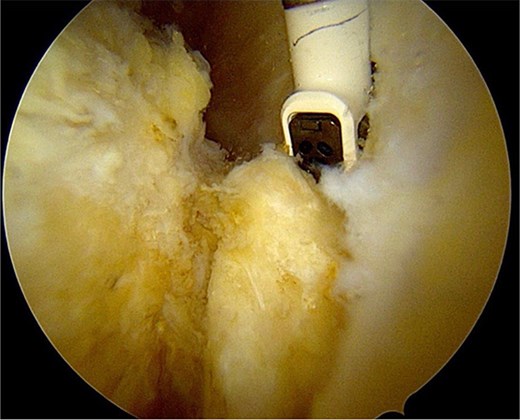

After partial resection of the infrapatellar fat pad for better visualization, the ossicle was exposed by finding the spinal needle and working around it. The fragment was freed arthroscopically using a motorized shaver and a radiofrequency probe (Fig. 5), taking care to protect the patellar tendon.

Once the ossicle was mobile and free (Fig. 6), it was removed either in one piece or was broken into multiple pieces with an arthroscopic burr and then removed with a grasper (Figs 7 and 8). Finally, the tibial tubercle was leveled using either an arthroscopic burr or shaver.

Arthroscopic views of case 1. (A) Ossicle fragment removed. Case 2 (B) tibial tubercle leveling using an arthroscopic Burr. Case 3 (C) ossicle fragment removed.